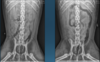

What is shown in these images?

A

left: normal canine stomach

right: normal feline stomach